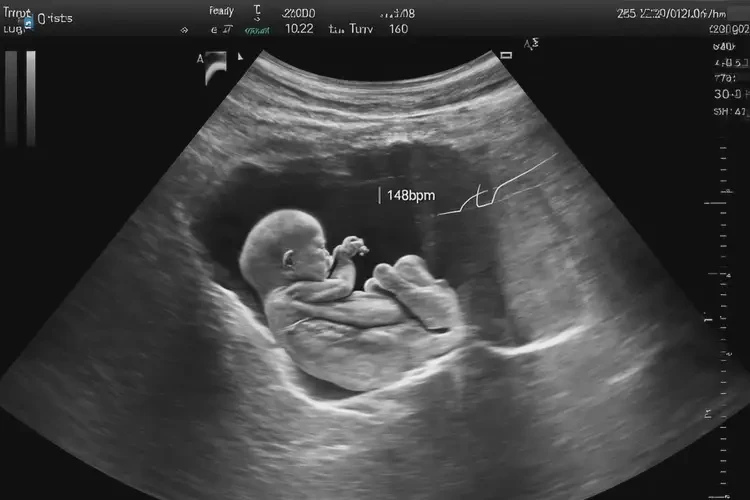

孕40周2天胎心78寶寶還能要嗎(圖1)

• 超聲檢查:觀察胎兒的生長發(fā)育情況,排除其他健康問題。